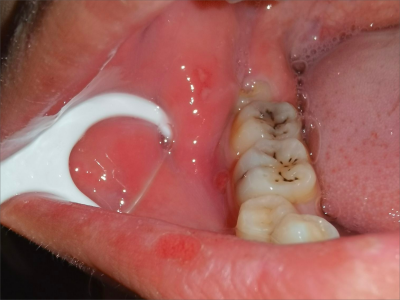

牙龈

溃疡

创伤性溃疡牙龈上出现一块黄白色溃疡图

创伤性溃疡不限唇、颊、舌,深浅不一,形状不规则,可在患者牙龈部位看到一块溃疡,呈黄白色糜烂,周围有炎性潮红,疼痛加重可见组织增生。